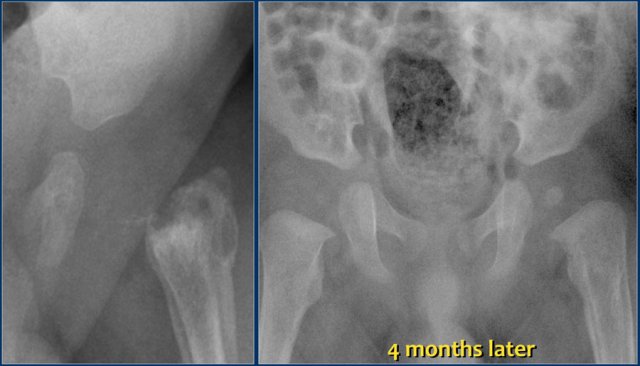

The images show:

- Collapse and sclerosis of the femoral head and metaphyseal lucency.

- Progression to fragmentation and development of a short, broad collum.

- Developing coxa magna deformity.